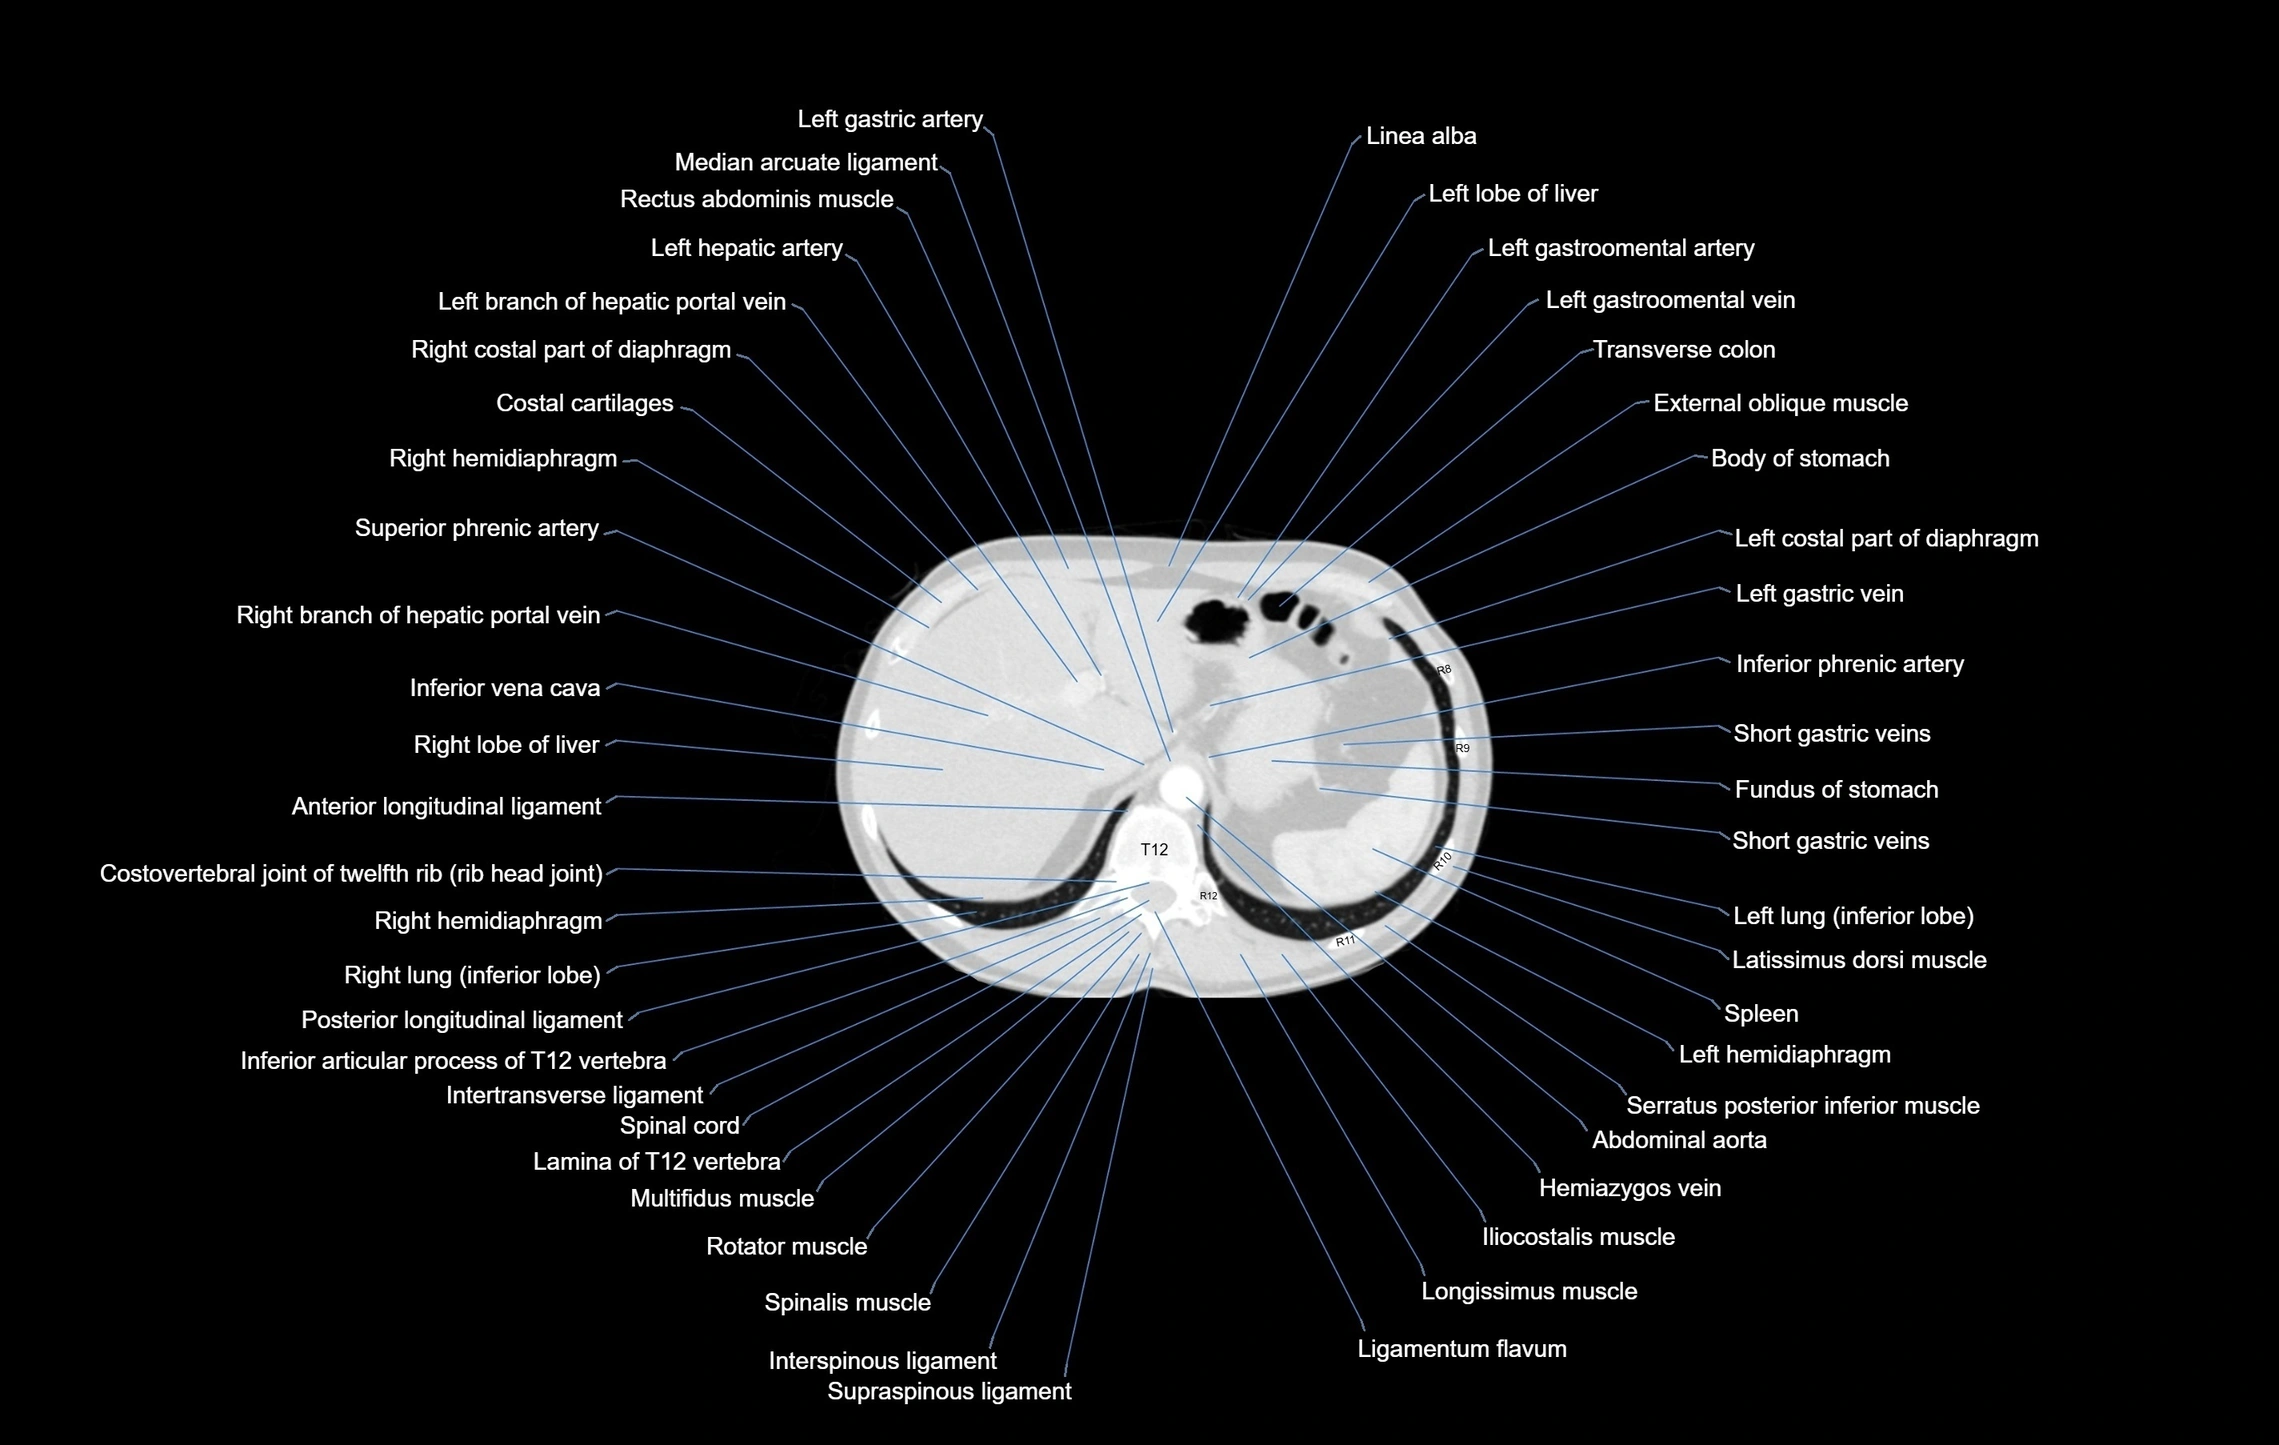

CT images